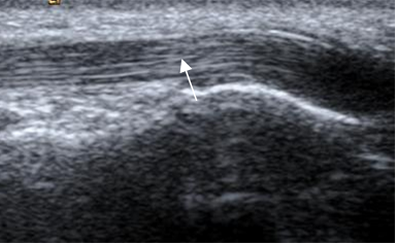

Fig 21. Fascia plantar normal en ecografía, corte sagital.